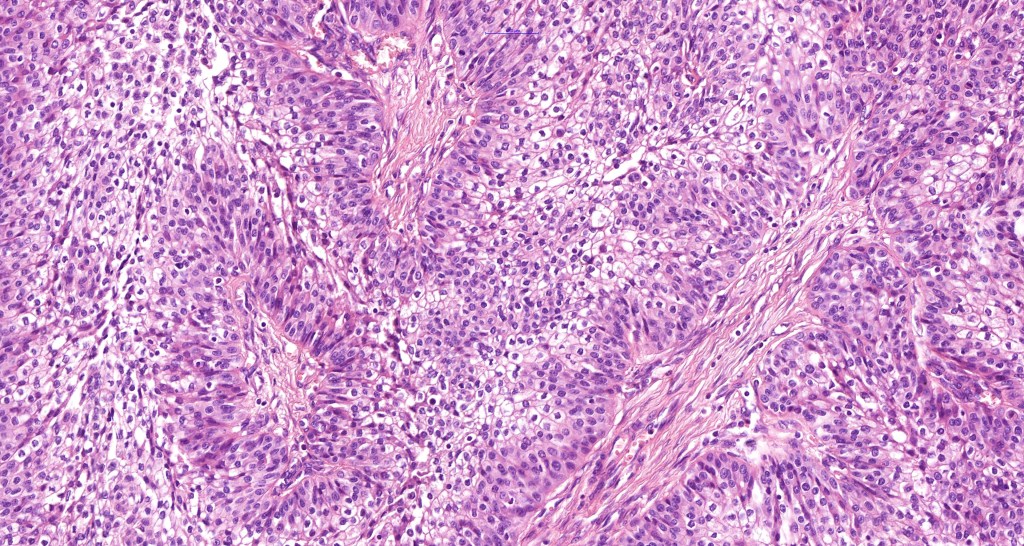

•Generally composed of an admixture of small eosinophilic cells & glycogen-rich larger clear cells

•Round to oval vesicular nuclei with small nucleoli or hyperchromatic nuclei

•No pleomorphism & scanty or no mitoses

•Atypical variant- nuclear pleomorphism, hyperchromatism, giant cells & increased mitotic activity (use very sparingly as risk of underdiagnosis of carcinoma is very high!)